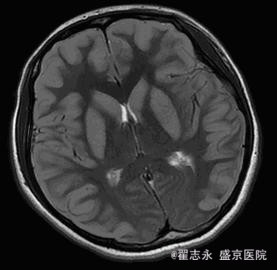

查体:昏迷,瞳孔等大,直径3.5mm,光反射迟钝。四肢疼痛刺激可见收缩反应。余查体不能配合完成。 头MRI的Flair及DWI如图。

诊断:缺血缺氧性脑病

新生儿缺血缺氧性脑病的早期表现有广泛脑水肿、颅内出血、皮质下及脑室旁白质损害、丘脑及基底节区和脑干背侧异常信号等; 晚期可表现为脑室周围脑白质软化症、分水岭区脑损伤等。而成人早期( 10 d 内) MRI 可表现为脑水肿、灰白质分界消失、大脑皮质层层状坏死、颅内出血; 晚期( 10 d~6 个月) 可表现为皮层下白质及深部白质脱髓鞘改变、选择性神经元坏死、广泛脑损害、脑萎缩。